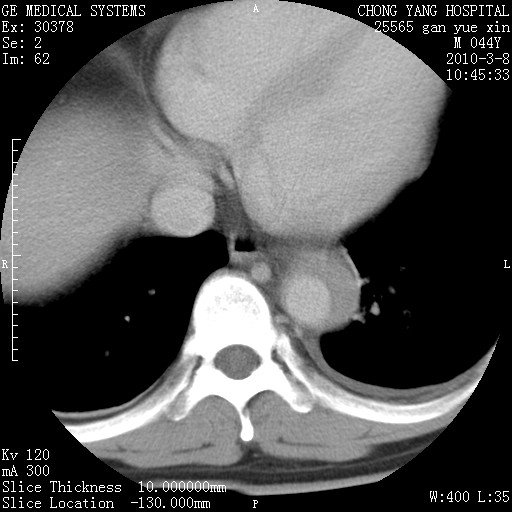

标题: CT24940:主动脉增强,典型病例。 [打印本页]

标题: CT24940:主动脉增强,典型病例。

夹层动脉瘤。

动脉夹层

夹层动脉瘤,典型

主动脉夹层。

动脉夹层的分型:

⒈debakey分型:根据主动脉夹层累及部位,分为三型:ⅰ型:原发破口位于升主动脉或主动脉弓部,夹层累及升主动脉、主动脉弓部、胸主动脉、腹主动脉大部或全部,少数可累及髂动脉。ⅱ型:原发破口位于升主动脉,夹层累及升主动脉,少数可累及部分主动脉弓。ⅲ型:原发破口位于左锁骨下动脉开口远端,根据夹层累及范围又分为ⅲa,ⅲb。ⅲa型:夹层累及胸主动脉。ⅲb型:夹层累及升主动脉、腹主动脉大部或全部。少数可累及髂动脉。

⒉stanford分型:a型:夹层累及升主动脉,无论远端范围如何。b型:夹层累及左锁骨下动脉开口以远的降主动脉。

夹层动脉瘤,少量胸水

夹层动脉瘤;左侧少量胸腔积液。

典型主动脉夹层。